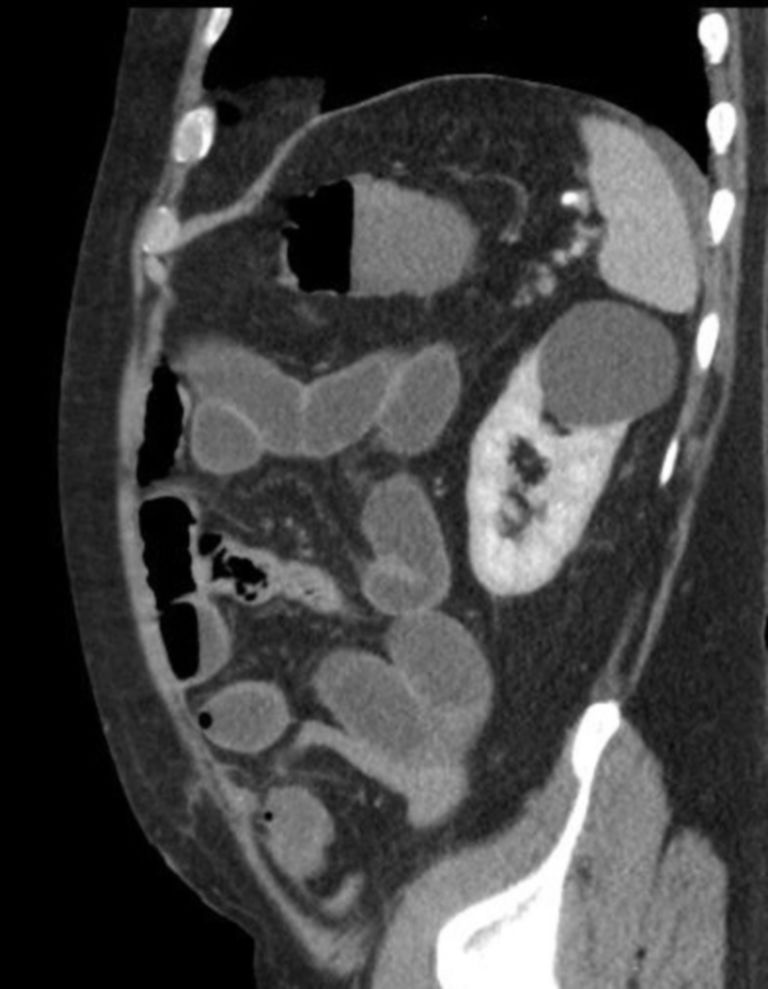

Coronal views of computed tomography scan of abdomen and pelvis with Frozen Abdomen Doccheck “it is commonly seen with. Frozen pelvis refers to a condition in which pelvic organs are distorted and tethered to each other as a consequence of adhesive processes. Rapid onset of severe abdominal symptoms potentially requiring surgical intervention. Acute abdomen refers to the rapid onset of severe symptoms of abdominal pathology. It may indicate a potentially life. Beim abdominellen kompartmentsyndrom. Frozen Abdomen Doccheck.